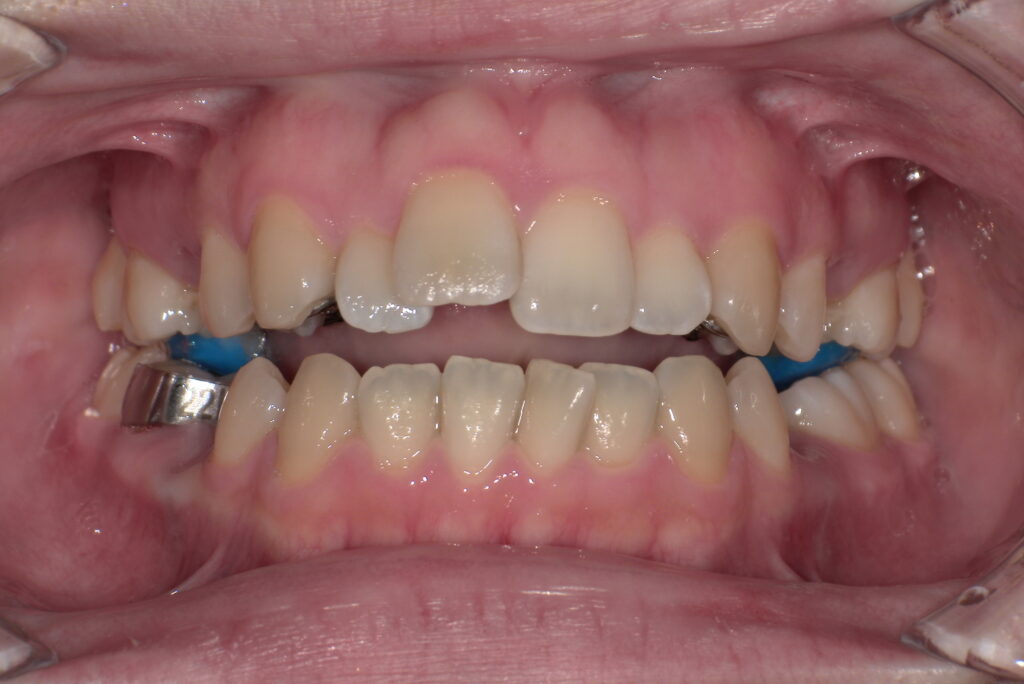

📸治療経過写真

当院で裏側矯正治療しているスタッフの経過写真をご参考にしてください。

上下左右小臼歯を1本ずつ計4本抜歯して現在も治療中です。「歯を抜いた隙間が閉じた量」、「前歯の移動量」、「正面から見た前歯の位置」に注目して見てもらえると、歯の移動の早さが目に見えて分かるかと思います。

初回装着時

正面

上顎

(青い材料は下の歯が上の装置にぶつからないよう、咬み合わせを一時的に上げる材料です)